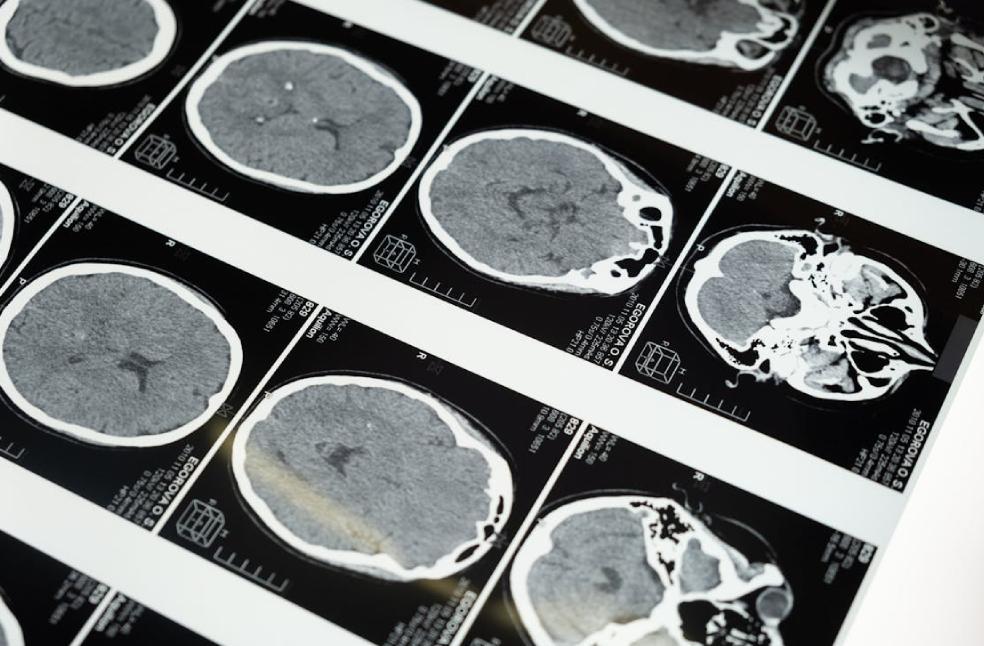

The research, conducted by a team of neuroscientists, has found that individuals exhibiting fanatical traits show reduced activation in the brain’s dorsal anterior cingulate cortex (dACC), a region essential for self-regulation and decision-making.

This aligns with prior research connecting the dACC to functions such as error monitoring, conflict detection, and adaptive learning, processes that enable humans to reconsider or adjust opinions when presented with new information.